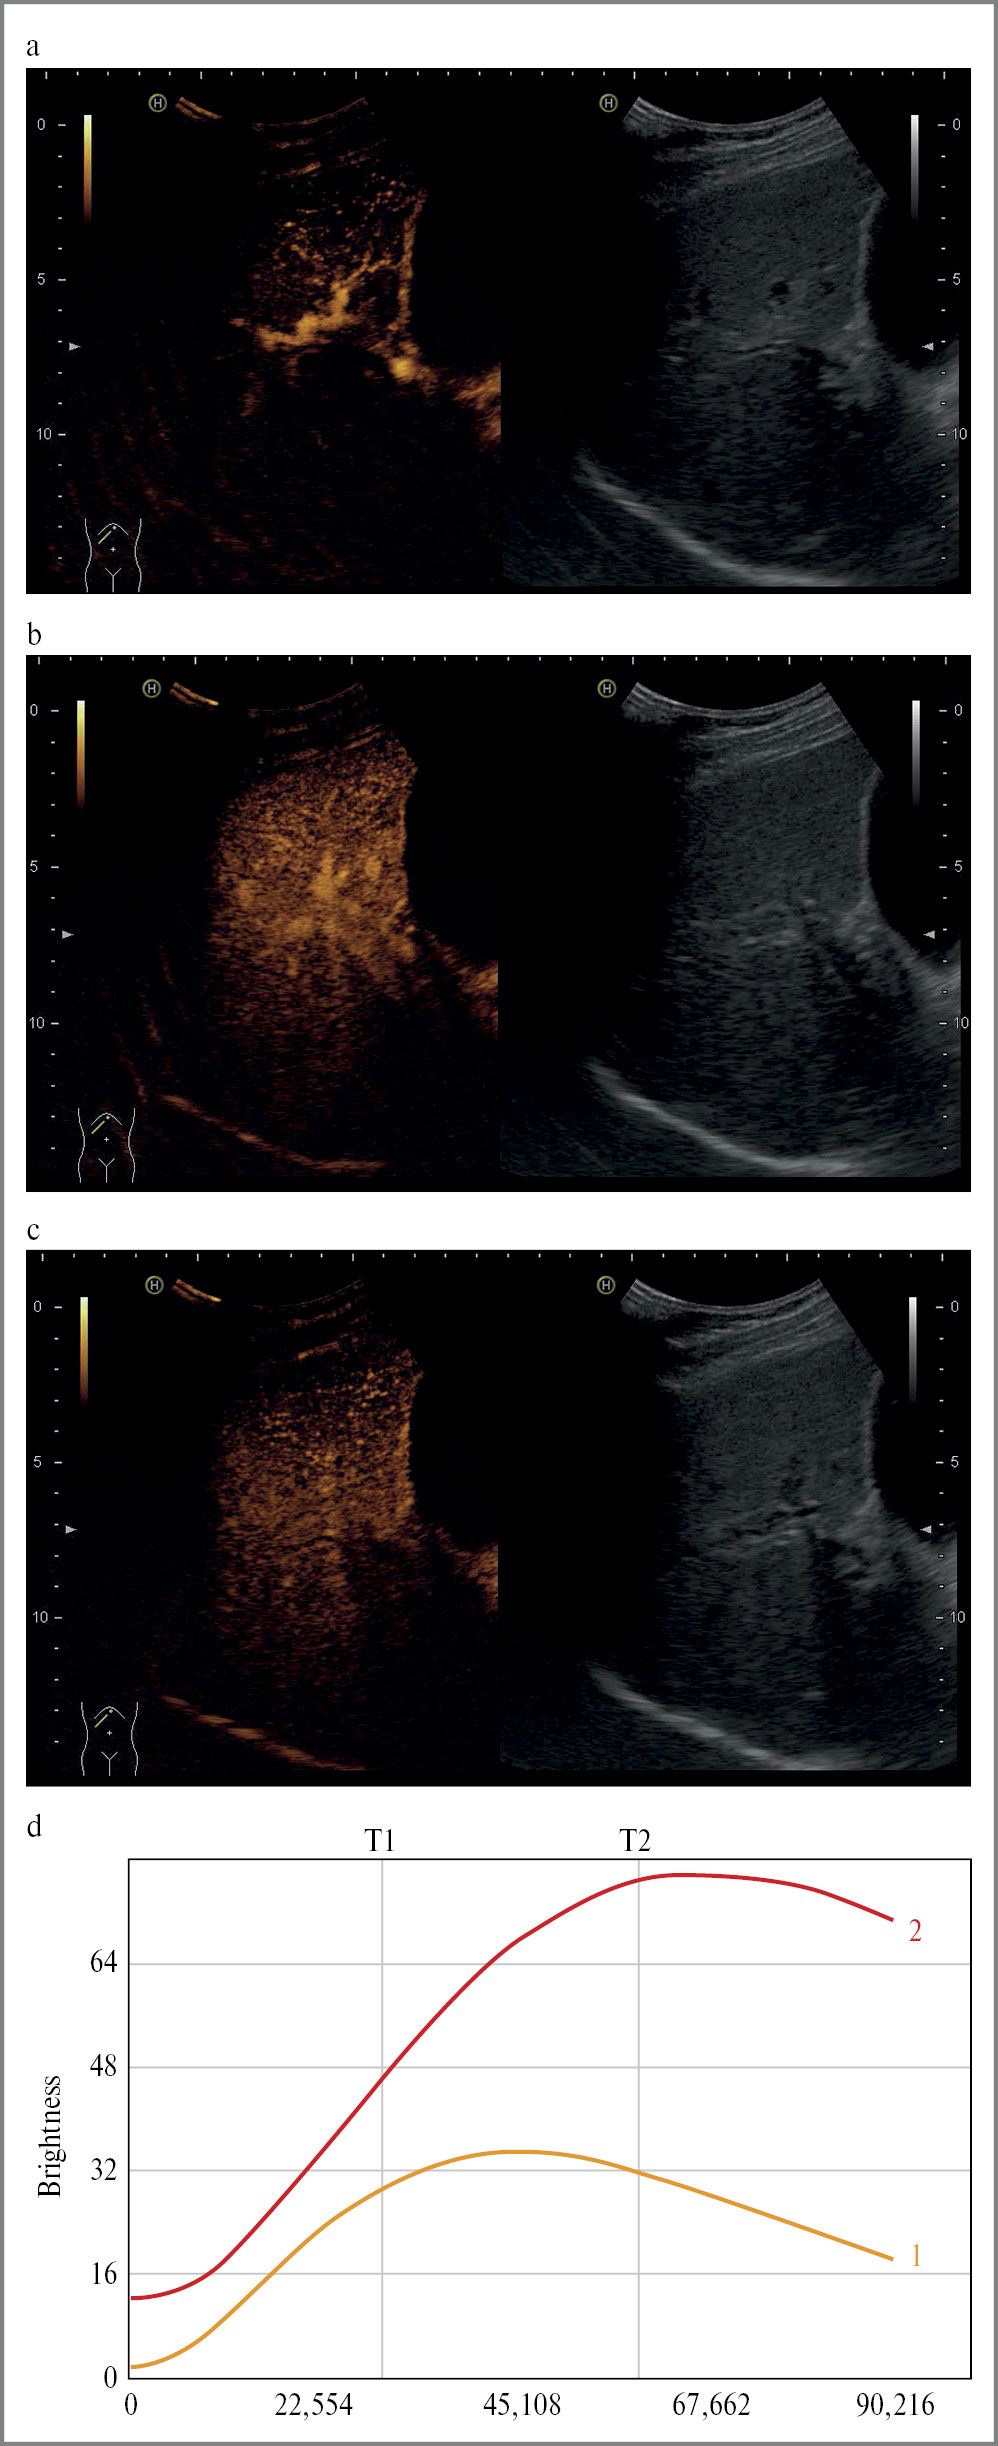

Всем пациентам с хроническими вирусными гепатитами С и В (n=120), как и пациентам контрольной группы (n=35), проведено КУУЗИ на ультразвуковом аппарате экспертного класса Hitachi Preirus конвексным датчиком (3,5 МГц) с использованием контрастного препарата II поколения, разрешенного к использованию в Российской Федерации, – SonoVue (Bracco Suisse S.A., Швейцария). Для предотвращения преждевременного разрушения и увеличения времени исследования устанавливали значения механического индекса для В-режима – 0,04, для режима Contrast – 0,06; 1,0 мл раствора гексафторида серы и 0,9% изотонического раствора хлорида натрия вводили в крупную периферическую вену, прежде всего в v. ulnaris sinistra, через 2-портовый периферический катетер диаметром G19-20. Во время исследования проводили запись контрастирования с непосредственной оценкой качественных параметров и анализом количественных параметров путем построения кривых накопления контрастного препарата в проксимальных и дистальных зонах в специализированной программе на ультразвуковом аппарате (рис. 1).

Рис. 1. Кривые накопления контрастного препарата: красная линия – проксимальная зона, желтая линия – дистальные зоны.

Примечание. Здесь и далее на рис. 2: ось ординат – яркость, дБ; ось абсцисс – время, с.

Fig. 1. Time intensity curves: red line – proximal zone, yellow line – distal zones.

При построении кривых накопления контрастного препарата в проксимальных и дистальных зонах у пациентов основной группы получены графики, отражающие значительную разницу показателей количественных параметров в проксимальных и дистальных зонах (рис. 2).

Рис. 2. КУУЗИ печени пациентов основной группы: а – артериальная фаза; b – портальная фаза; c – поздняя венозная фаза; d – кривые накопления контрастного препарата: красная линия – проксимальная зона, желтая линия – дистальные зоны.

Fig. 2. Contrast-enhanced ultrasound in the main group: a – arterial phase; b – portal phase; c – late venous phase; d – time intensity curves: red line – proximal zone, yellow line-distal zones.